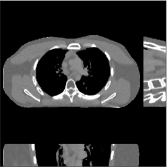

This section compares the reconstruction quality and runtime among the proposed MBIR method, PWLS-ST-, and other three MBIR methods, PWLS-EP, PWLS-DL, and PWLS-ST-. Table I shows that, for both 2D and 3D sparse-view CT reconstructions of the XCAT phantom, the proposed PWLS-ST- model outperforms PWLS-EP and PWLS-ST- in terms of RMSE. In addition, PWLS-ST- using a square transform (of size ) achieves lower RMSE than PWLS-DL using an overcomplete dictionary (of size ) for 2D sparse-view reconstructions. Fig. 3(a) and Fig. 4 show the reconstructed images for 2D and 3D phantom experiments, with different reconstruction models and different number of views. (See the corresponding error maps in the supplement.) The proposed PWLS-ST- consistently gives more accurate image reconstructions compared to other MBIR methods. Specifically, PWLS-ST- has smaller errors in the heart region (see zoom-ins in Fig. 3(a)) of 2D reconstructions than PWLS-DL and PWLS-ST-. In addition, compared to PWLS-ST-, PWLS-DL and PWLS-ST- have some ringing artifacts around the edges with high transition, e.g., edges between air and soft tissues. (See a comparison of profiles of PWLS-ST- and PWLS-ST- in the supplement.) In particular, PWLS-ST- and PWLS-DL give more visible ringing artifacts for 2D reconstruction from fewer views, and PWLS-ST- has these ringing artifacts for 3D reconstructions regardless of the number of views (see zoom-ins in Fig. 4). Table II reports runtimes of different MBIR methods in reconstructing the -views XCAT phantom scan. (FBPConvNet is a non-MBIR method and its runtime for processing a image is approximately one second with a TITAN Xp GPU.) While providing better reconstruction quality, the proposed Algorithm 1 of PWLS-ST- has shorter runtime compared to the algorithms of PWLS-DL and PWLS-ST- in Section III-A. Similar to the PWLS-EP algorithm, the reconstruction time of the PWLS-DL, PWLS-ST-, and PWLS-ST- algorithms can be further reduced by using ordered subsets [51].

Fig. 3(b) shows that when tested on the clinical scan data, the proposed PWLS-ST- method improves reconstruction quality in terms of noise and artifacts removal (e.g., see zoom-ins for soft-issue regions), and edge preservation (e.g., see zoom-ins for bone regions), compared to PWLS-EP and PWLS-ST-. Compared to PWLS-DL, PWLS-ST- achieves comparable image quality, but requires less computational complexity.

| (a) 2D fan-beam CT experiments |

| (b) 3D axial cone-beam CT experiments |